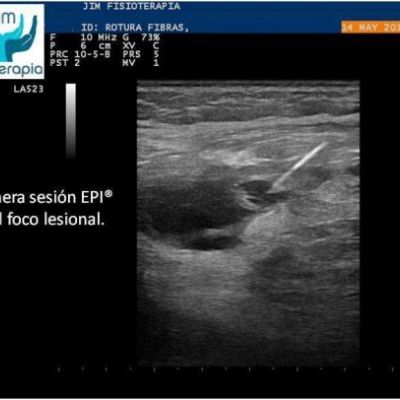

Varón de 47 años, sufre una rotura muscular en el bíceps femoral de la pierna derecha al realizar una brusca contracción excéntrica asociada a movimiento de torsión, al evitar la caída de su motocicleta. Acude a las 72 hrs a nuestra clínica presentando dolor a la palpación, contracción muscular y en la marcha. En la exploración ecográfica se observa una rotura de bordes irregulares.

Se procede a la aplicación de EPI® con el fin de “vaporizar” el derrame producido y favorecer el proceso de regeneración y cicatrización muscular sin fibrosis. En las imágenes se puede apreciar el cambio en el tejido desde la primera sesión, fueron necesarias cuatro sesiones de EPI® hasta lograr la recuperación completa, a partir de la segunda sesión el paciente refirió una desaparición del dolor en la marcha y las actividades cotidianas, complementando su tratamiento con la aplicación de Radiofrecuencia.